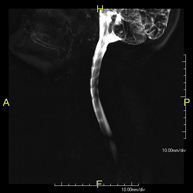

- MRI Myelography

This non-invasive diagnostic procedure uses an electromagnetic field and radio waves (from a transmitter and receiver) to acquire high-definition anatomical images of the spinal cord and nerve roots. It is a radiation-free procedure. Indicated for: hernias, spinal cord compression.